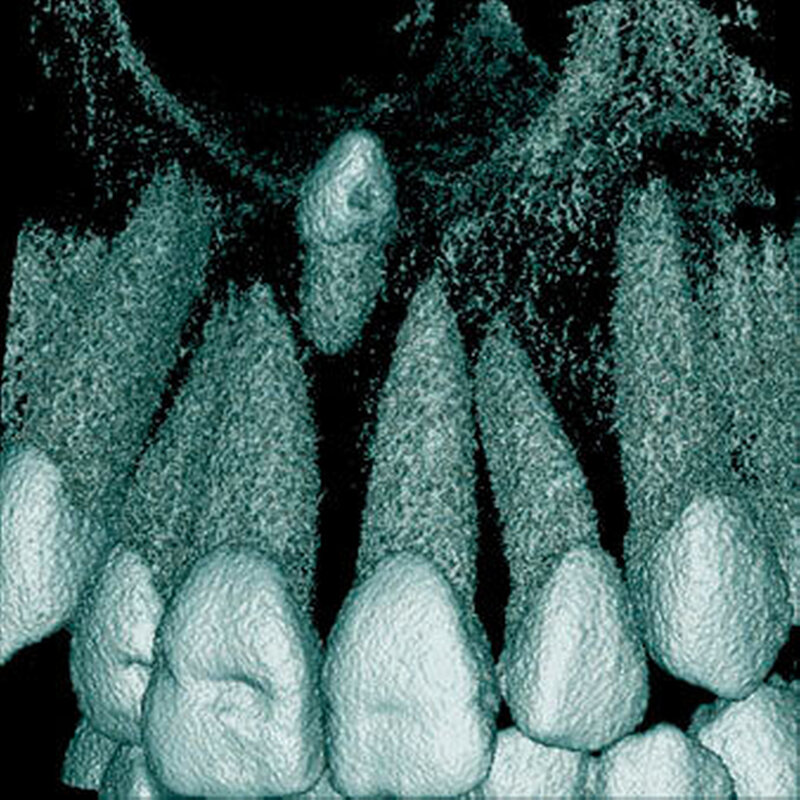

Überzählige Zähne sind die häufigste Ursache für einen unterbliebenen oder verzögerten Durchbruch der oberen Schneidezähne (Abbildungen 13, 14, 15) [Betts Camilleri, 1999]. Besonders beim höckerförmigen Typ kommt es häufig zu Störungen der Eruption der oberen Schneidezähne [Mason et al., 2000]. Diese Komplikation macht sich klinisch initial dadurch bemerkbar, dass die oberen seitlichen Schneidezähne durchbrechen und die Eruption von einem oder beiden zentralen Schneidezähnen ausbleibt [Rajab Hamdan, 2002]. Auch in anderen Lokalisationen der Kiefer können überzählige Zähne zu Durchbruchsstörungen benachbarter Zähne führen [Garvey et al., 1999; Rajab Hamdan, 2002; Mossaz et al., 2014]. Insgesamt liegt die Prävalenz für den Ausfall des Durchbruchs bleibender Zähne bedingt durch überzählige Zähne zwischen 10,2 Prozent und 61 Prozent [Tay et al., 1984; Koch et al., 1986; Tyrologou et al., 2005; Fernández Montenegro et al., 2006; Liu et al., 2007; Gündüz et al., 2008; Hyun et al., 2009; Mínguez-Martinez et al., 2012; Mossaz et al., 2014].

Überzählige Zähne werden nach ihrer Lage im Zahnbogen und auch aufgrund ihrer Morphologie eingeteilt. Basierend auf der Lage unterscheidet man bei überzähligen Zähnen zwischen Mesiodens (Oberkiefer median), zwischen den zentralen Inzisiven (Abbildungen 5 und 6), einem zusätzlichen Schneidezahn (zentral oder lateral), Eckzahn, Prämolar (Abbildung 7), Paramolar und Distomolar (Abbildungen 8). Mesiodentes werden am häufigsten dia- gnostiziert, wobei Prozentsätze zwischen 38,8 Prozent bis 86,3 Prozent der überzähligen Zähne in der Literatur zu finden sind [Salcido-García et al., 2004/38,8 Prozent, Fernández Montenegro et al., 2006 /46.9 Prozent; Mossaz et al., 2014/48.5 Prozent; Ferrés-Padró et al., 2009/53.2 Prozent; Schmuckli et al., 2010/75 Prozent; Rajab Hamdan 2002/83.2 Prozent; Liu et al., 2007/86.3 Prozent]. Überzählige Prämolaren und seitliche Schneidezähne sind die zweithäufigste Gruppe der überzähligen Zähne. Überzählige Eckzähne, Paramolaren und Distomolaren dagegen gelten als eher selten [Rajab Hamdan, 2002; Salcido- García et al., 2004; Liu et al., 2007; Ferrés-Padró et al., 2009; Schmuckli et al., 2010; Mossaz et al., 2014]. Einzig eine Spanische Gruppe [Fernández Montenegro et. al., 2006] berichtete, dass Paramolaren und Distomolaren insgesamt relativ häufig seien (18 Prozent, beziehungsweise 5,6 Prozent). Überzählige Zähne kommen im Ober- und Unterkiefer vor, wobei sich überzählige Schneidezähne in der Regel im Oberkiefer, überzählige Prämolaren sich dagegen eher im Unterkiefer befinden [Fernández Montenegro et al., 2006; Ferrés-Padró et al., 2009; Mossaz et al., 2014]. Überzählige Molaren wiederum treten normalerweise im Oberkiefer auf [Cassetta et al., 2014; Kaya et al., 2014].